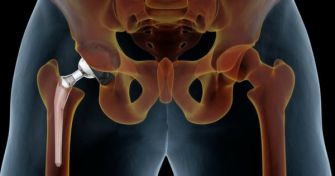

Prothesen: Der Alltagsretter nach Gelenkschäden

Dank optimierter Materialien und Operationstechniken lässt sich heute fast jedes Gelenk ersetzen. Spitzenreiter sind nach wie vor Hüft- und Kniegelenke. Früher galten Gelenkprothesen als letzter Ausweg bei alten, kranken Menschen. Heute wird immer früher das Messer angesetzt. Jeder 10. Patient ist unter 65. Wer achtsam mit der Prothese ...

Diagnose Hüft-Arthrose: Wege in ein beschwerdefreies Leben

Leichte Schmerzen in der Hüfte und gelegentliche Bewegungseinschränkungen? Verantwortlich dafür können erste Abnutzungserscheinungen im Hüftgelenk sein, die Sie im schlimmsten Fall dazu veranlassen, eine Operation in Erwägung zu ziehen. Was schadet der Hüfte? Alles über die Hüftarthrose. ...